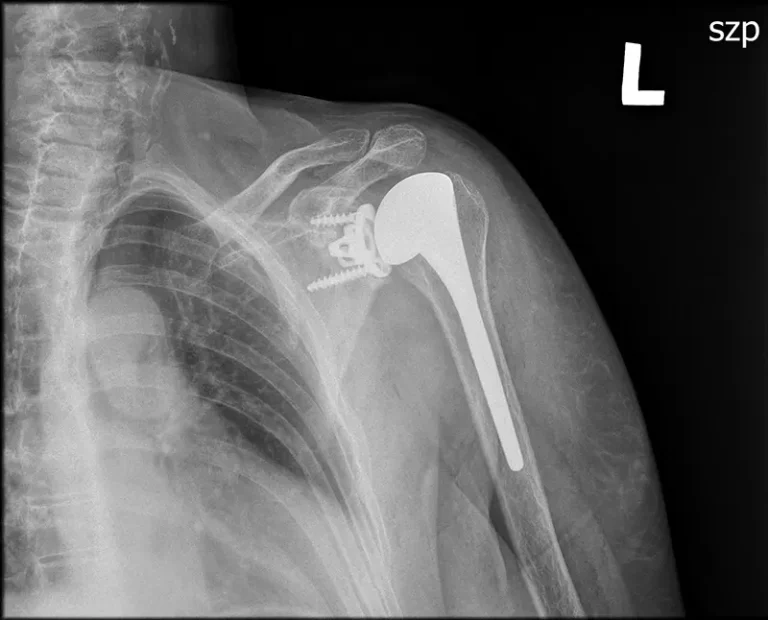

3. Odwrócona proteza stawu ramiennego

Jak nazwa wskazuje, polega na odwróceniu elementów stawu ramiennego. Stosujemy ją w ekscentrycznych zmianach zwyrodnieniowych stawów w przebiegu uszkodzenia stożka stawu ramiennego.

Polega ona na tym, że w miejscu panewki stawu ramiennego montujemy metalową bazę, na której montuje metalową półkulę – nową głowę protezy. Natomiast w części ramiennej po jej przygotowaniu/odpowiedniemu docięciu montujemy trzpień, na którym zakładamy panewkę.

Po nastawieniu stawu uzyskujemy zwiększenie przestrzeni podbarkowej, poprawienie stabilizacji stawu, oraz dzięki mięśniu naramiennemu prawidłowy zakres ruchomości operowanego stawu.